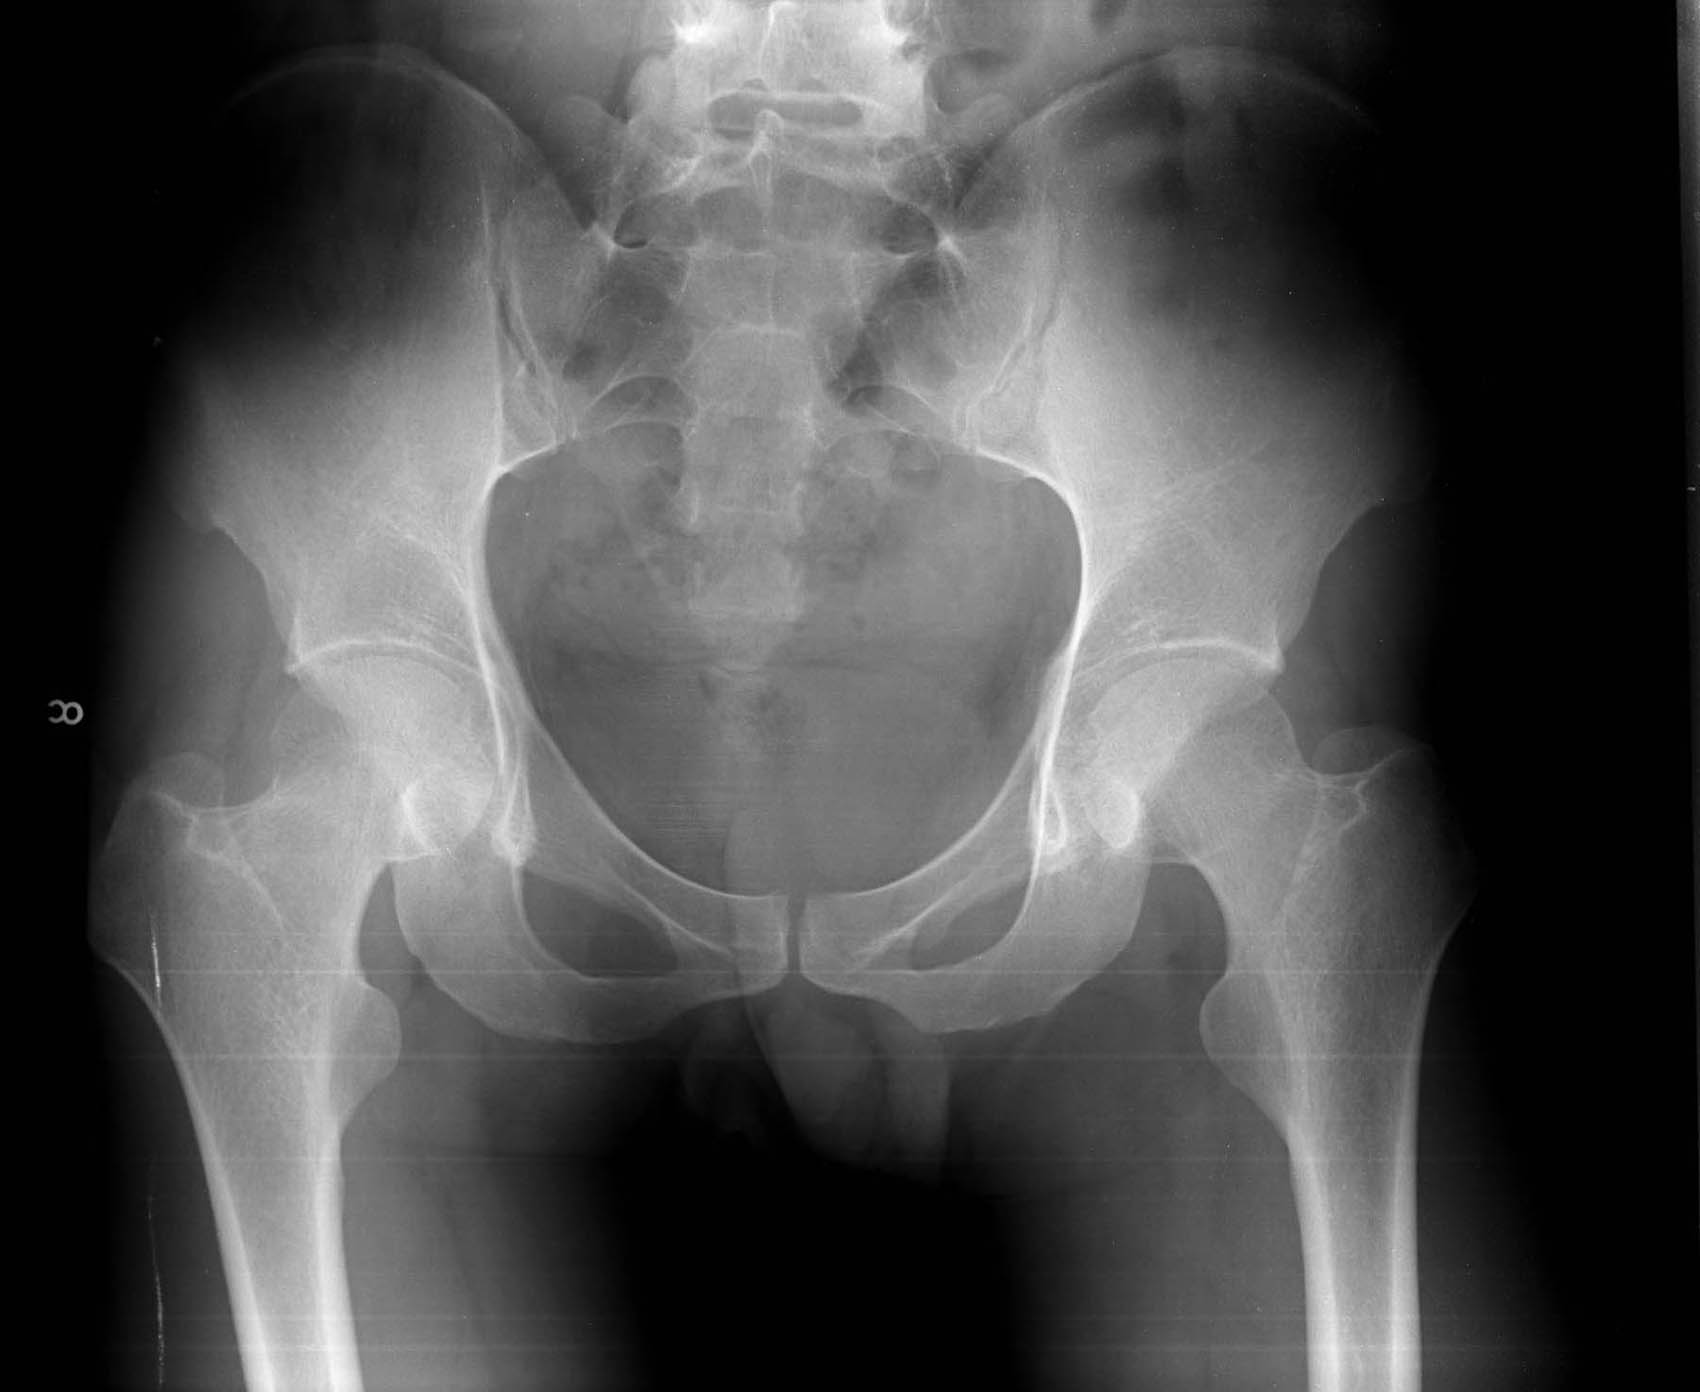

x线看到一点不对 左侧髋臼骨皮质有点欠连续!对比右侧看看

x线看到的太有限了

学习了  x线看不到 谢谢楼主